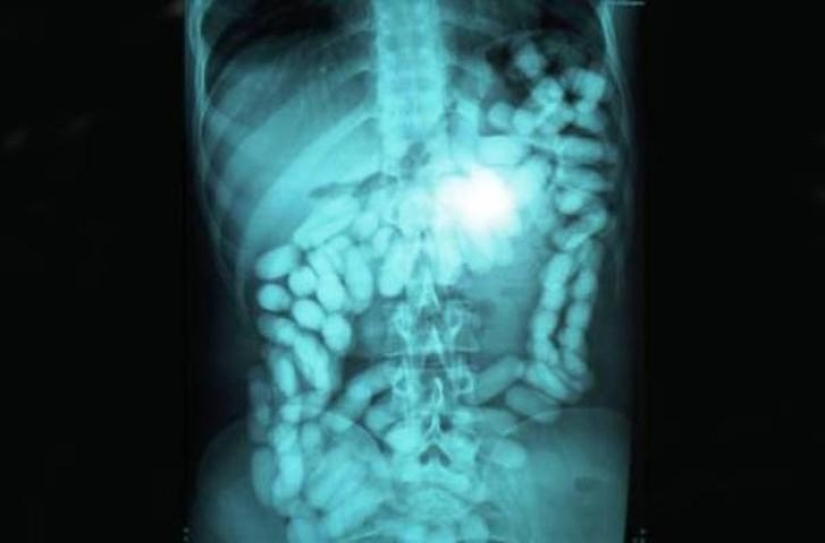

17. Una enorme bola de lana.